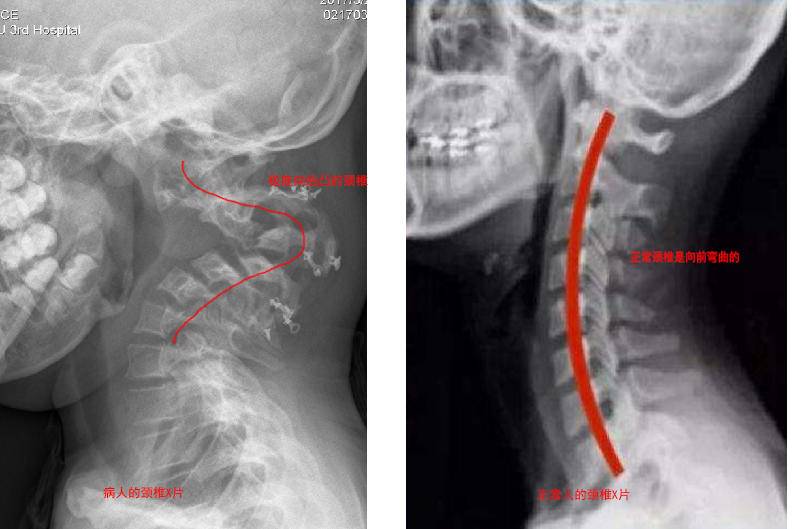

正常颈椎是稍微向前方弯曲的,这是为了直立行走。但是,这个孩子的颈椎严重向后弯曲,这在医学上叫做严重的颈椎后凸畸形。

一方面,脖子支撑不住头的重量,头会把畸形弯曲的颈椎压得越来越弯,所以他抬不起头。

另一方面,畸形的颈椎会压迫颈部的脊髓、气管、食管、血管。现在是两条腿没劲儿,再进展四肢都可能瘫痪。